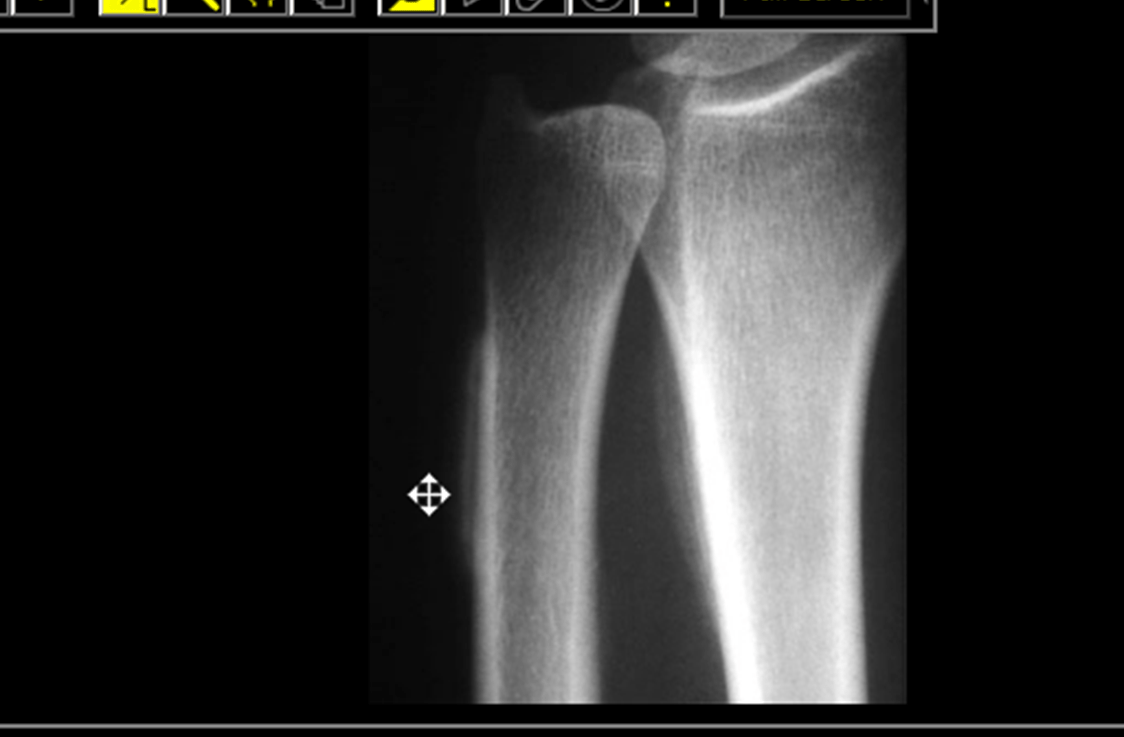

You see this x ray and then recommend this further imaging:

What is chest imaging? Hypertrophic Pulmonary Osteoarthropathy